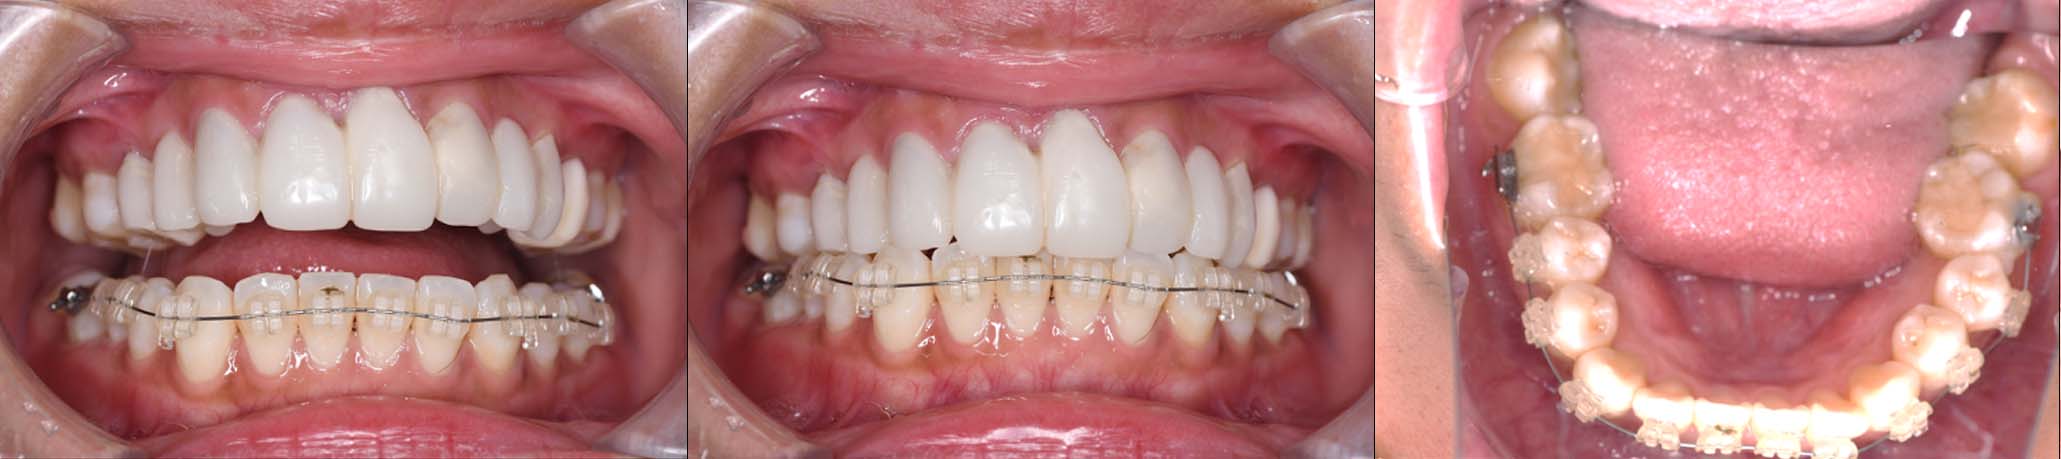

| 治療内容 | ①スプリントを装着 ②副子を装着 ③2024年4月 口腔内反映開始 ④副子を入れた状態の所まで咬合を挙上 (バイトアップ) ⑤2024年5月 上顎前歯部8本へ仮歯(TEK) を装着 |

バイトアップ後